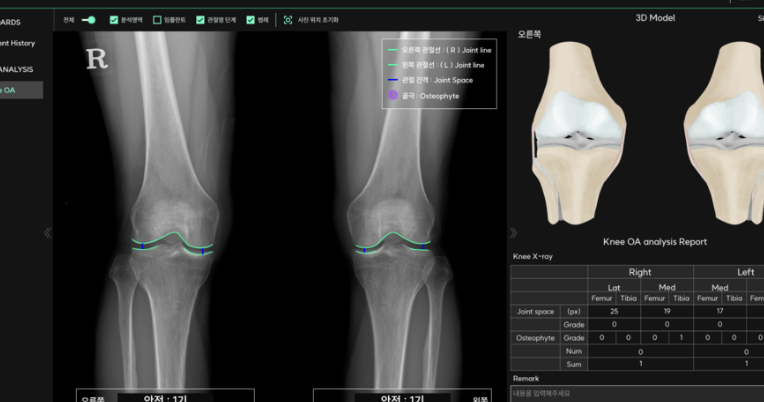

Korean companies are also actively participating in the surgical robot market. Connective Co., Ltd. (CEO: Doohyun Noh) successfully raised KRW 4 billion (Pre-A) after being recognized for its AI-based joint replacement surgical robot technology. Connective develops robots that perform highly precise joint replacement surgeries using AI, as well as solutions that analyze artificial joints using X-ray imaging. With this investment, the company plans to expand its workforce to develop next-generation surgical robots and pursue medical device regulatory approval for its AI-based musculoskeletal diagnostic support software. Going forward, it aims to build high-quality AI technology using more than 100,000 images directly labeled by specialist physicians at university hospitals.

[Fig] Connective Co., Ltd.’s AI-Based X-ray Joint Analysis Solution